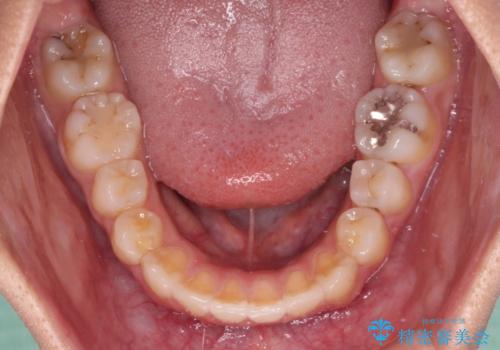

- 下顎の前突感と前歯の叢生を気にして来院された患者様です。

下顎前方位の骨格のため、下顎歯列に対して上顎歯列の幅が狭くなっていました。

急速拡大装置を用いて上顎骨を側方に拡大し、上顎の叢生を解消するとともに下顎歯列拡大により下顎の叢生も解消することとしました。